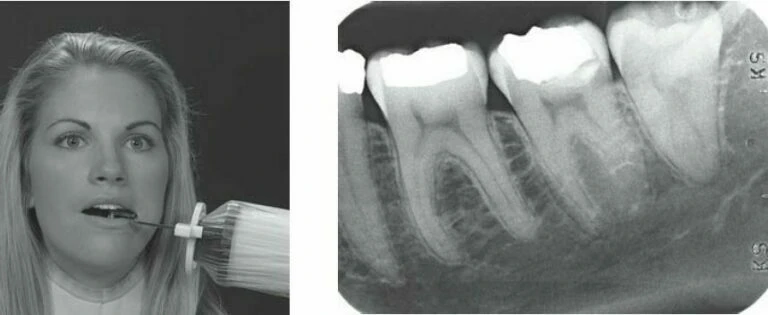

Đọc tiếp1. Bệnh nhân nam 39 tuổi tới khám vì lý do cắn vỡ một phần răng 47 có nhu cầu…